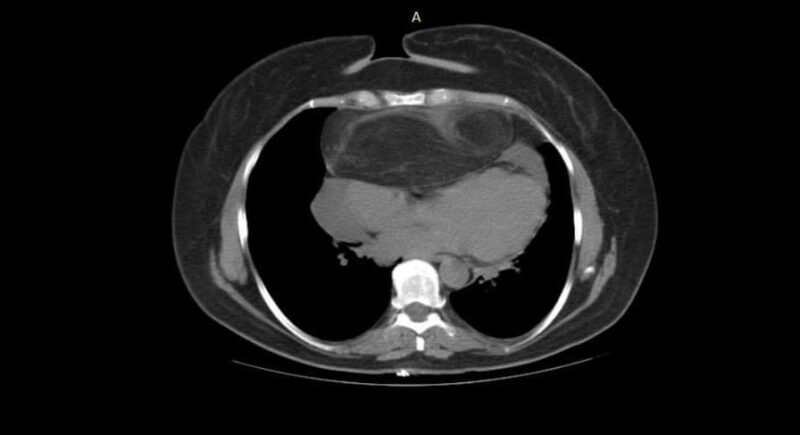

“В мене з’явилась задишка і кашель. Пройшла обстеження та була в шоці! Адже, крім черевної порожнини як зазвичай, моя пухлина розташовувалась попереду серця та сильно його здавлювала. Це викликало задишку навіть при незначних рухах.  Я оббивала пороги лікарень в Україні та навіть за кордоном, але ніхто не наважувався мене оперувати”, — розповідає Оксана.

Наважились бодай спробувати допомогти жінці у рідному Львові. Для цього зібрали цілий консиліум з найкращих спеціалістів Лікарні Святого Пантелеймона. Мультидисциплінарна команда кілька разів збиралася, аби зважити всі “за” та “проти” операції. Ризики були високі, адже пухлина вже доросла до серця та проходила занадто близько до перикарду і великих судин. Їхнє пошкодження – це неминуча смерть пацієнтки просто на операційному столі. Утім, якщо не оперувати, жінка точно помре. Тож вирішили все ж спробувати її врятувати та розробили ретельний план складного втручання.

“Пацієнтка дуже важка. Крім 5-кілограмової пухлини в черевній порожнині і середостінні, в неї були і супутні захворювання, які відтерміновували операцію. Зокрема – це вірусне захворювання та анемія. Рівень гемоглобіну був лише 27, коли в нормі має бути 120-140. Тож спершу ми мали підготувати організм пацієнтки до того, аби вона змогла пережити цю операцію”, — пояснює Юрій Шаваров, провідний спеціаліст Центру хірургії Лікарні Святого Пантелеймона.